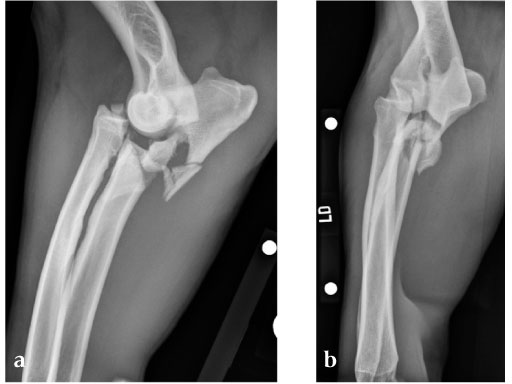

5-year-old male English Mastiff, road traffic accident.

(Case provided by Michael P Kowaleski, North Grafton, USA)